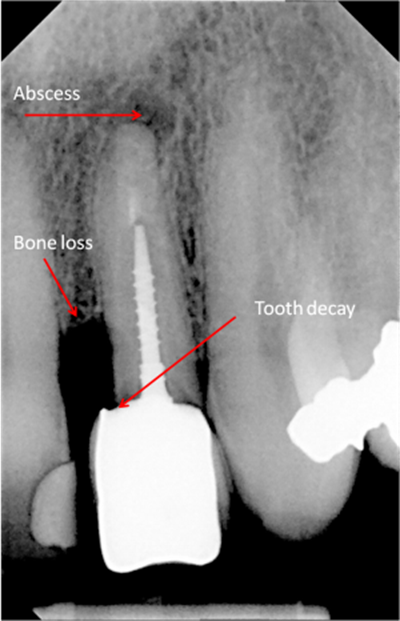

Digital x-rays can be used to diagnose:

- Cysts of jawbone

- Bone loss

- Decay between teeth